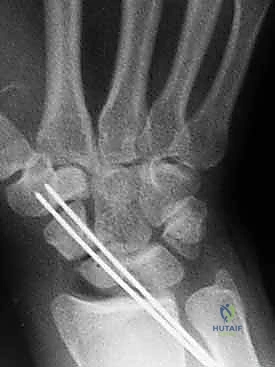

هذه هي المرحلة الحاسمة. يستخدم الدكتور هطيف أحدث التقنيات العالمية، وتحديداً "براغي الضغط بدون رأس" (Headless Compression Screws) مثل برغي هيربرت (Herbert Screw). يتم تمرير سلك توجيهي (K-wire) دقيق عبر الكسر لضمان الاستقامة، ثم يتم إدخال البرغي المجوف فوق السلك.

يقوم هذا البرغي المبتكر بضغط جزئي الكسر معاً بقوة شديدة، وبما أنه "بدون رأس"، فإنه يغوص بالكامل داخل العظم ولا يبرز ليحتك بغضاريف المفصل المحيطة.

6. الإغلاق والتأكيد الإشعاعي

أثناء الجراحة، يتم استخدام جهاز الأشعة السينية المتنقل (C-arm) للتأكد من الموضع المثالي للبرغي والاصطفاف التام للعظم. بعد التأكد، يتم خياطة الأنسجة والجلد بدقة تجميلية، ووضع جبيرة خفيفة.